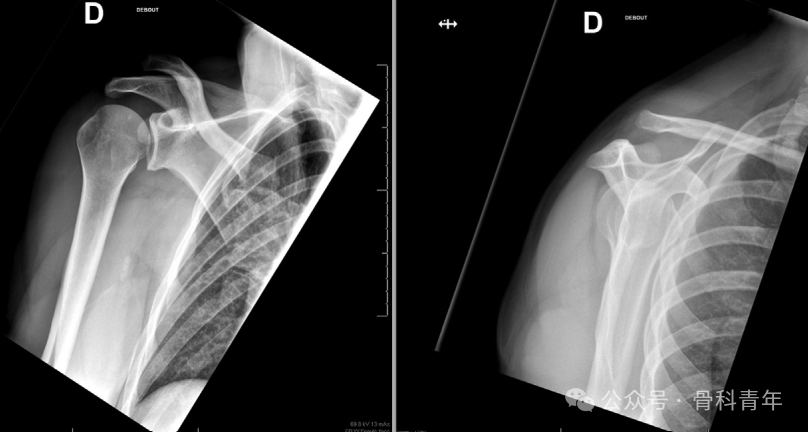

肩锁关节脱位是临床常见疾病,对Rockwood III-VI型肩锁关节脱位,为恢复肩锁关节稳定性及肩部正常活动,通常建议手术治疗。目前,肩锁关节脱位的手术内固定包括切开复位内固定(钩钢板、Tightrope)与关节镜下微创固定技术。

开放手术常规需显露分离三角肌以显露深层结构,软组织损伤较大。国外学者介绍了一种经三角肌胸大肌入路改良术式,保留完整三角肌,为肩锁关节稳定术提供更优的手术入路选择。本文分享该技术,供骨科医师参考: